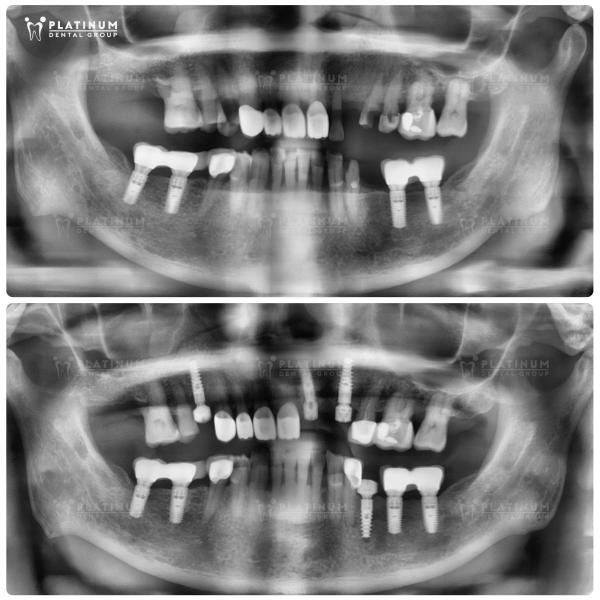

Step 1: Comprehensive Examination, 3D CT X-Ray, 3D Scan, and Consultation with Dentist

At the initial stage, the dentist will perform a general oral health check, take X-ray and 3D CT scans to accurately assess bone density and the Implant site. A 3D digital impression is also taken to plan the most suitable restoration according to your mouth structure.

Based on the diagnostic results, the dentist will provide detailed consultation on the treatment method, the number of Implants needed, duration, cost, and whether bone grafting is required.